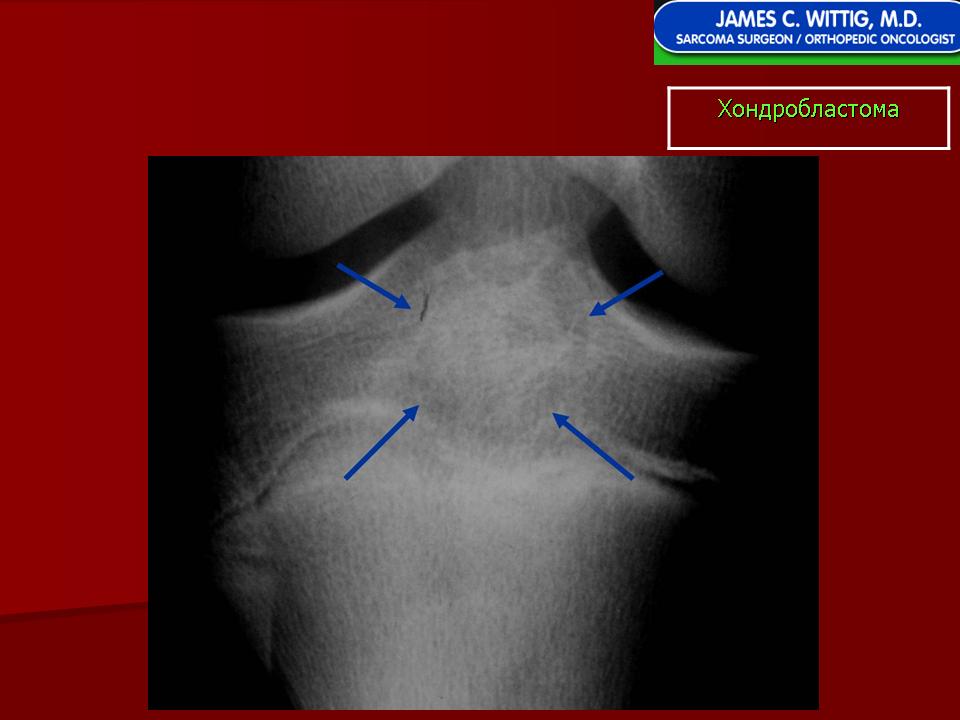

Хондробластома — это редкая доброкачественная опухоль, локализующаяся, главным образом, в эпифизе и отличающаяся своеобразным клеточным составом. Ткань новообразования представлена овальными, округлыми и веретеновидными клетками, напоминающими незрелые хондроциты (хондробласты). Зрелый гиалиновый хрящ определяется лишь в некоторых опухолях. Возраст больных варьирует. Мужчины поражаются в два раза чаше женщин. Пациенты предъявляют жалобы на боли в течение нескольких месяцев или лет, у некоторых больных определяются внутрисуставной выпот, припухлость и ограничение движений. Наиболее типичная локализация опухоли — проксимальные эпифизы плечевой и большеберцовой костей, а также дистальный эпифиз бедренной кости. У 20 % больных опухоль развивается в плоских или коротких трубчатых костях, преимущественно в пяточной и таранной. Изредка поражаются кости лицевого черепа, в том числе височная. В большинстве случаев новообразование выходит за пределы эпифиза и распространяется на метафиз. На фоне остеолиза обнаруживаются рассеянные участки обызвествления в виде пунктирных линий, а также разреженный трабекулярный рисунок. Хондробластома, как правило, не выходит за пределы кости, но изредка проникает в полость сустава. В процессе роста опухоли иногда возникает вторичная аневризматическая костная киста.

Рентгенологически хондробластома представляет собой сравнительно большой (2-4 см) очаг округлой формы, четко отграниченный от окружающей кости склеротической каймой. На фоне очага в большинстве случаев, но не обязательно определяются плотные включения, напоминающие хлопья ваты.

Рентгенологическая картина. Хондробластома выглядит как небольшой, от 3 до 6 см литический очаг, центрально или эксцентрично расположенный, с четкими контурами, занимающий около половины площади эпифизарной зоны. Хондробластома плоских костей и мелких трубчатых костей больших размеров, может сопровождаться припухлостью мягких тканей, вздутием кости и периостальной реакцией. Распространение процесса на метафизарную зону встречается часто.